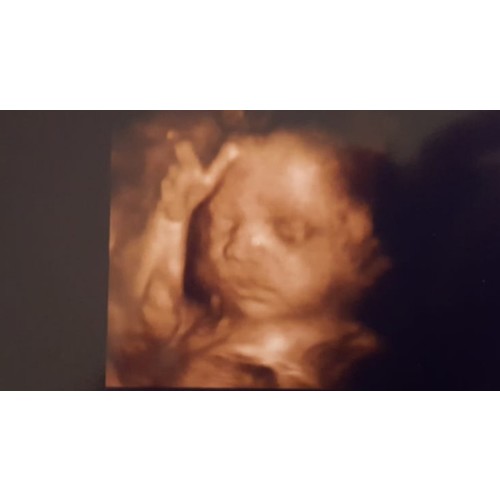

Misschien een idee om dit bij je verloskundige neer te leggen hoe jij erover denk/voel? Dan ben je het voor jezelf kwijt.. ik denk dat je ook een soort voornemen moet hebben van baby kan vroeg of laat rondom 1 tot 7 maart komen, zou dat je misschien gerust kunnen stellen?? 🤗 btw die echofoto is awesome